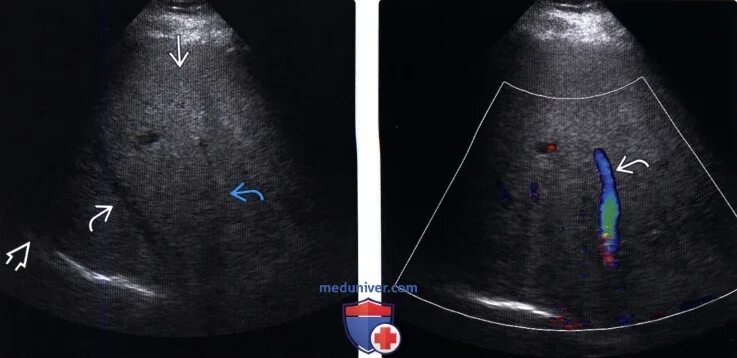

Диффузные изменения паренхимы по типу стеатоза